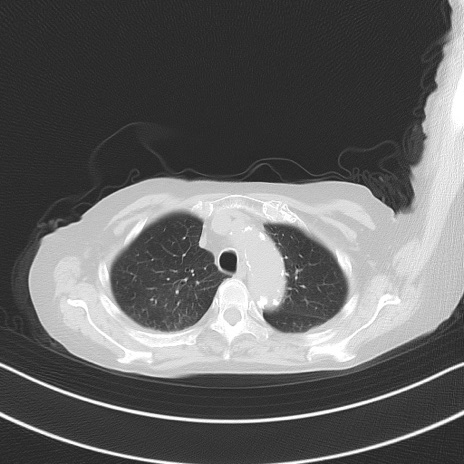

横断像

冠状断像